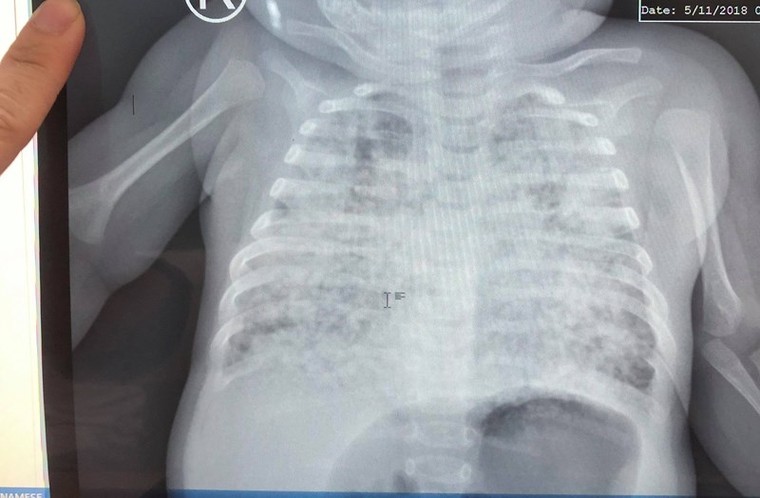

Phim phổi tổn thương trắng xóa, lấm tấm do lao kê của bé khi mới nhập viện điều trị - Ảnh: Pháp luật TP.HCM

Thông tin từ VTC News cho biết, đó là trường hợp của V.T.N (5 tháng tuổi, quê An Giang). Bệnh nhi nhập viện trong tình trạng nhiễm lao kê nặng, phổi trắng xoá, kén khí do các ổ lao vỡ liên tục gây tràn khí màng phổi những 4 lần, thở máy kéo dài, suy hô hấp nặng lệ. Tình trạng của bé nguy kịch đến nỗi các bác sĩ tưởng chừng bé không còn cơ hội sống.